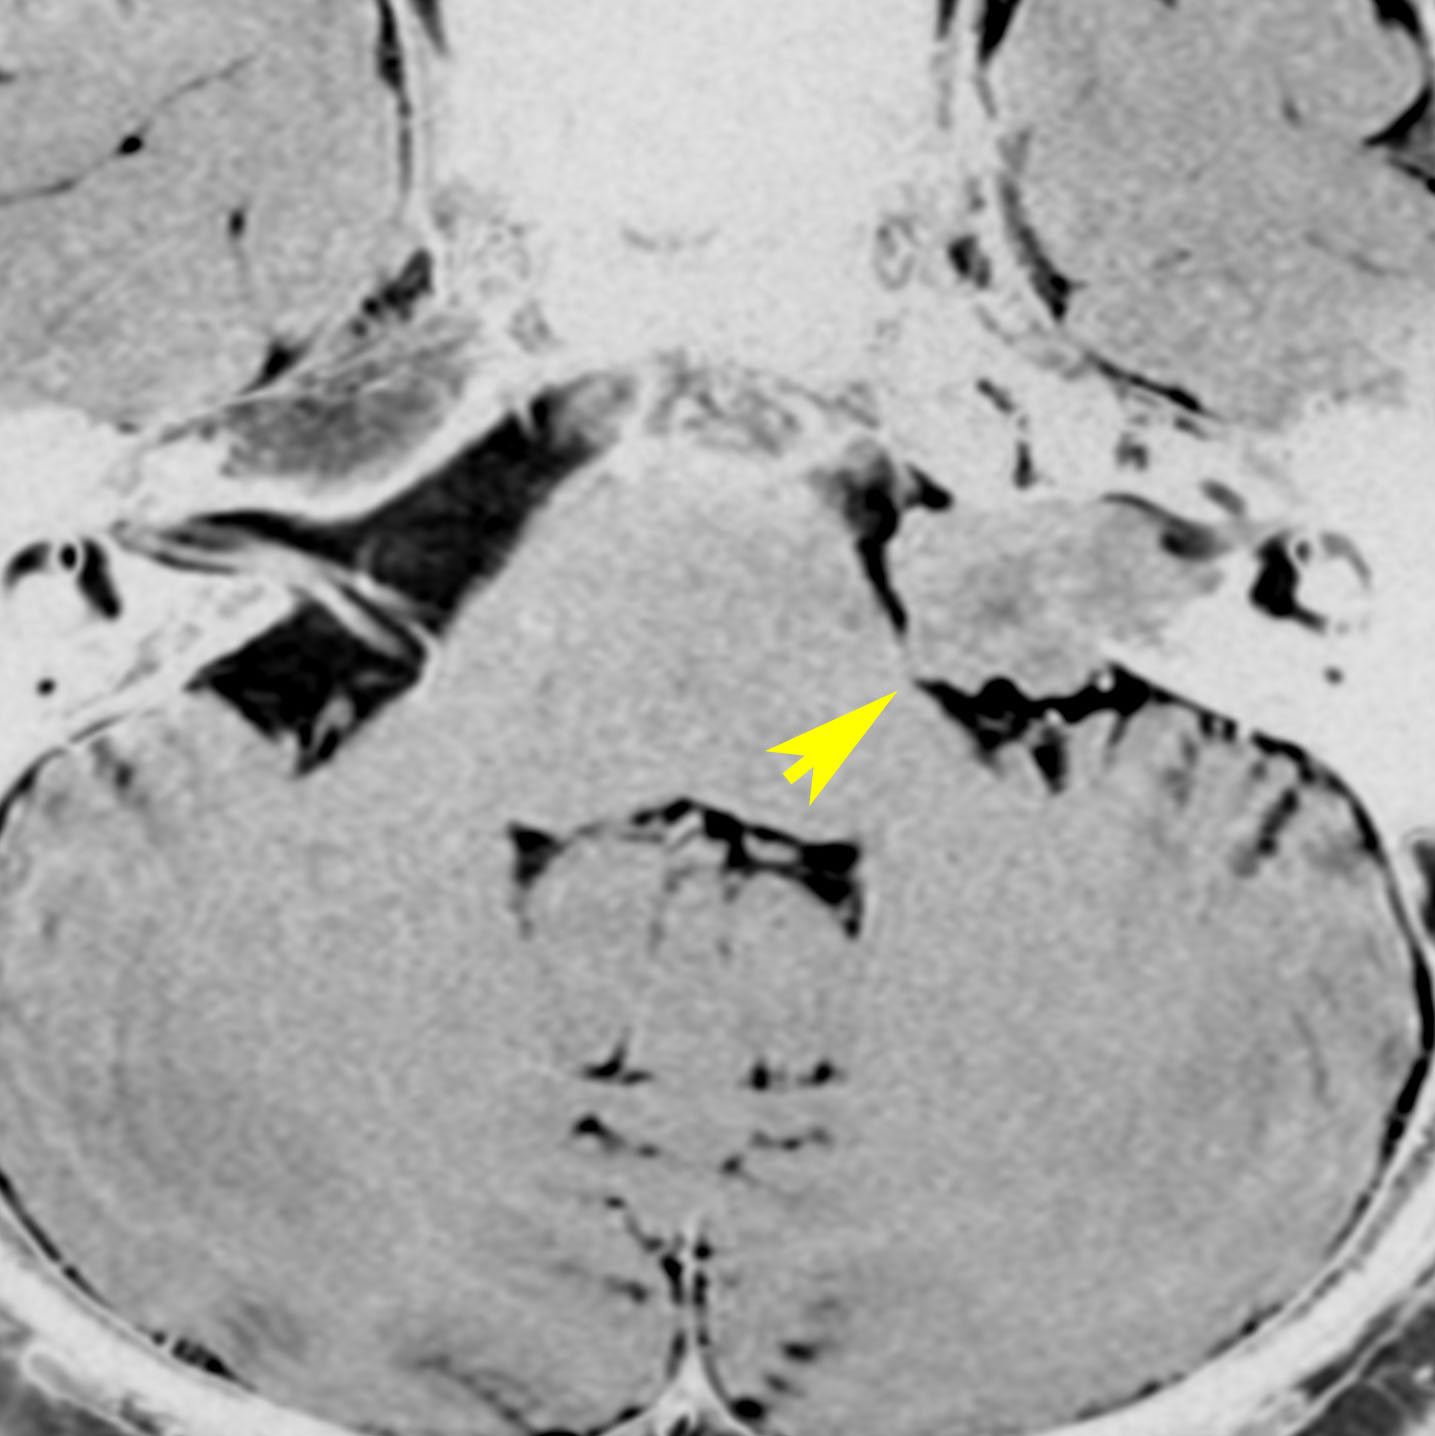

大きなのう胞性聴神経腫瘍です。いくつかの袋が重なって腫瘍を形成しています。橋や延髄(脳幹部)が変形して,第4脳室がつぶれて閉塞しています。袋の周りが白く線状に造影されているのですが,この袋の壁だけに腫瘍細胞がありますから,これを剥がすように摘出します。顔面神経が薄くなって袋の壁にくっついているのですが,袋を破ってくしゃくしゃにすると顔面神経の位置が変わってしまって,顔面神経を損傷することがあるので要注意です。のう胞性聴神経腫瘍の方が顔面神経麻痺の後遺症の頻度が高いという報告もあるくらいです。この患者さんは迷走神経と舌咽神経の圧迫も強くて,ご飯を飲み込むことが難しくなっていました(嚥下障害)。

また,この患者さんは急に容態が悪くなって意識障害となりました。何故なら腫瘍の内部で出血したからです(黄色の矢印の部分)。第4脳室が詰まって閉塞性水頭症になって側脳室が拡大しています(右の画像)。